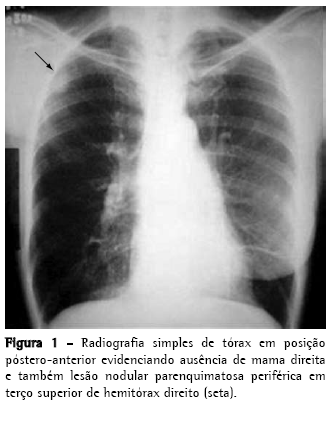

Foi então realizada tomografia computadorizada de tórax que identificou um nódulo pulmonar pleuro-parenquimatoso de aproximadamente 30 × 25 mm (Figura 2) em pulmão direito. Assim foi aventada a hipótese de metástase pulmonar do carcinoma de mama previamente operado, sendo indicada biópsia para confirmação diagnóstica.